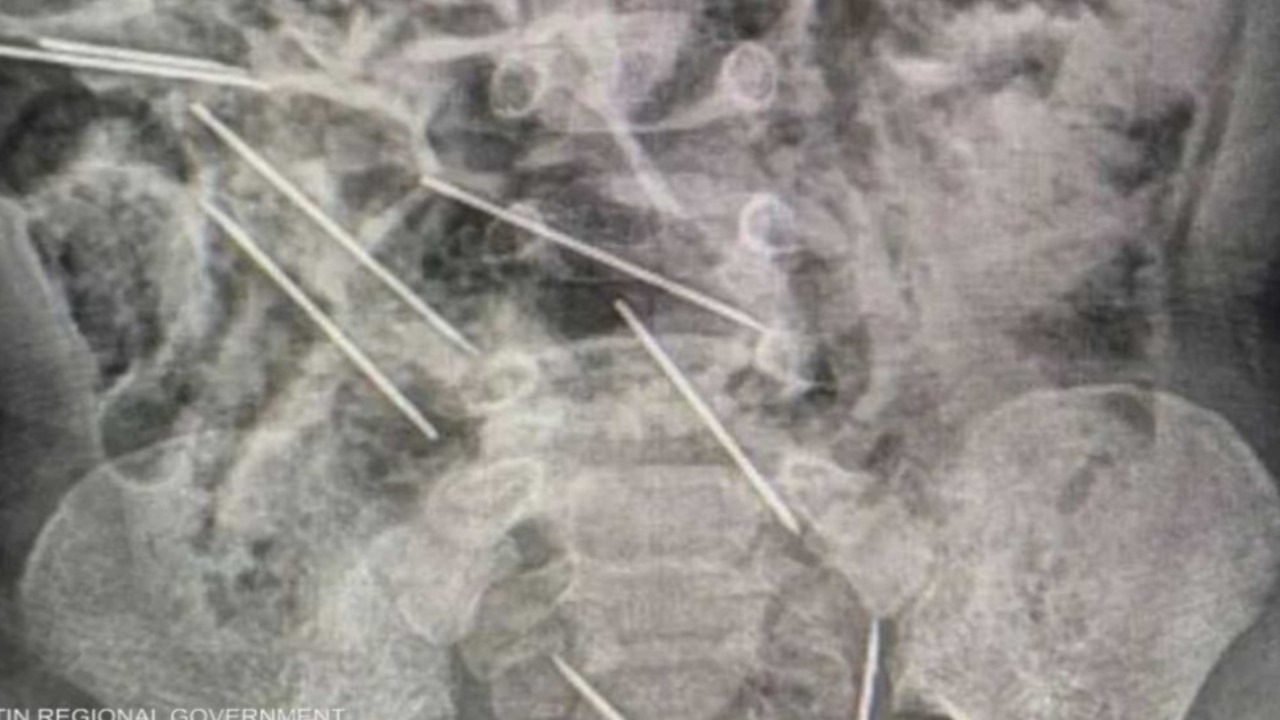

طفل يبتلع 8 إبر حقن مخصصة للحيوانات